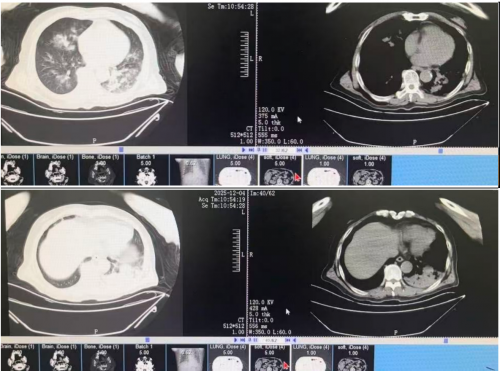

2025-12-04 胸部CT:

12月6日肺泡灌洗液NGS结果提示肺炎链球菌 37333*10^9/L, 肺炎克雷伯杆菌 554*10^3/L,甲型流感病毒H3N2 10783*10^6/L

降钙素原14.89 ng/ml。

晨测动脉血气(FiO250%):PH7.431,PO2 110mmHg,PCO234.5mmHg,HB90g/L,K 3.2mmol/l, Ca+ 1.09mmol/L, Na 144mmol/L, Glu 14.6mol/L, Lac 2.0mmol/L, HCO3- 23.0mmol/L,BE -1.0mmol/L。